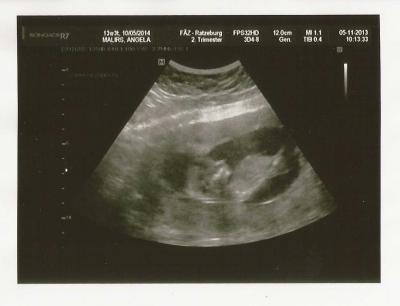

heute VU gehabt... alles in bester Ordnung... Mäuschen hat ordentlich gehüpft und das Herz hat ordentlich geschlagen... Bei mir wird ja jedesmal US gemacht, da ich Risiko bin... größe von Kopf bis Po: 6,5 cm ich selbst hab 1 kg abgenommen...

Bild zu VU gehabt - Forum für Mai - Mamis

Sorry falscher nickname.... 13+3